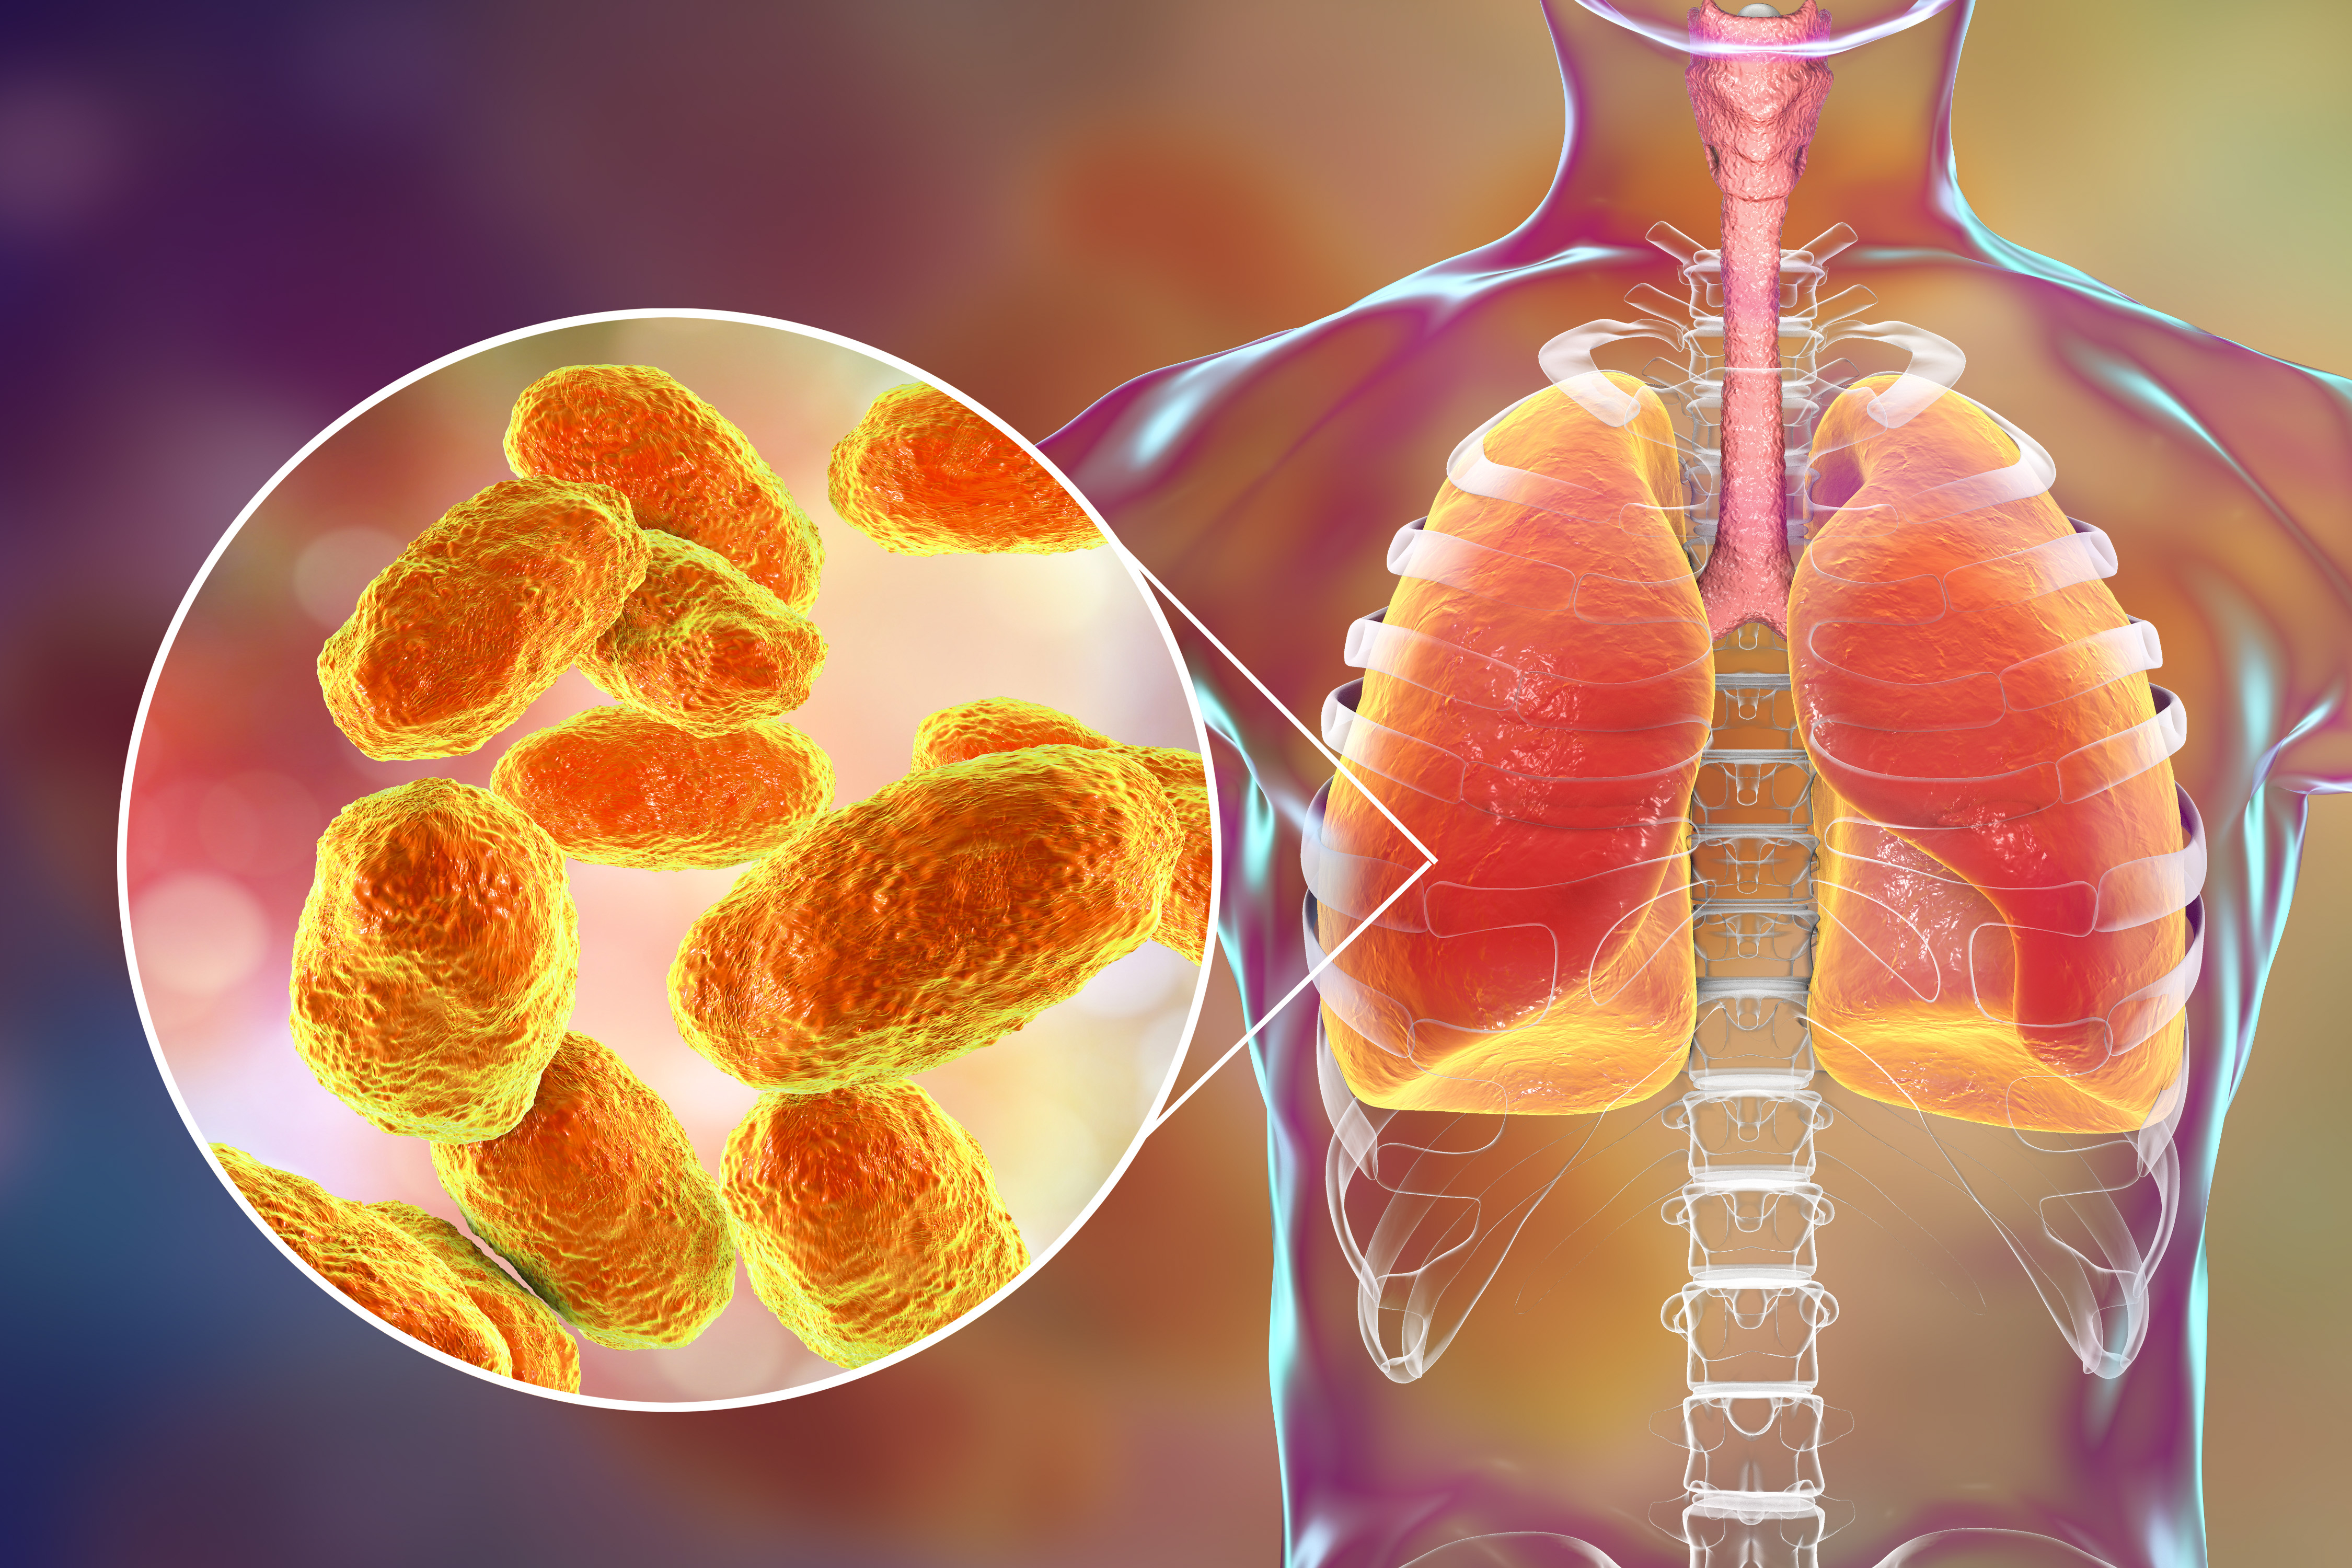

Фотографии бактерий, вызывающих бактериальные пневмонии у животных